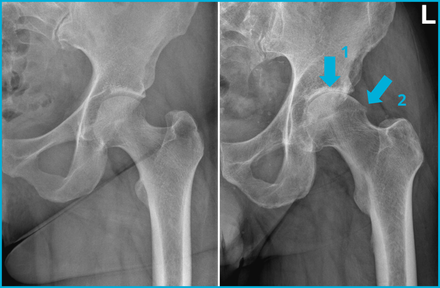

- Aanvullend onderzoek / beeldvorming: daarnaast maakt een arts een röntgenfoto. Op de röntgenfoto kijkt de arts of er afwijkingen van het heupgewricht te zien zijn, zoals artrose. Eventueel zijn er nog aanvullende scans mogelijk, bijvoorbeeld een CT- of een MRI-scan.

De afbeelding laat twee röntgenfoto’s van een linkerheup zien. Op de linkerfoto zie je een normale heup. Op de rechterfoto zie je een heup met artrose. Dit is te zien aan de gewrichtsspleetversmalling (pijl 1) en een osteofyt bij de overgang van de kop naar de hals (pijl 2). Ook is er sclerose zichtbaar bij pijl 1.